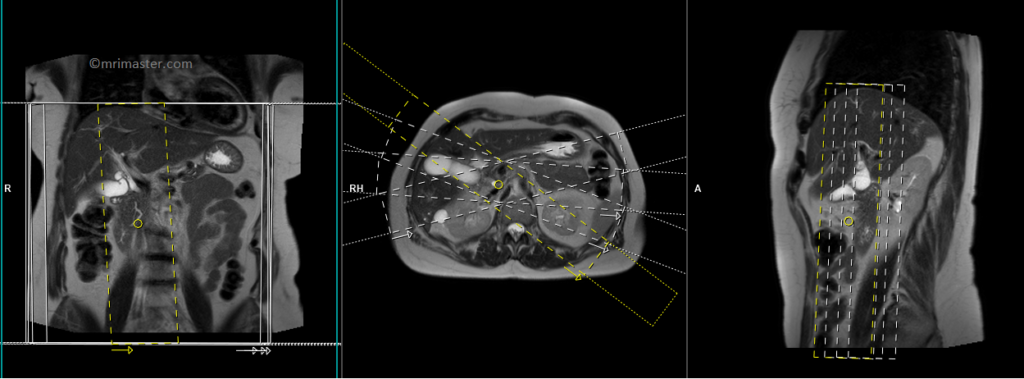

T2 SPACE 3D(or T2 TSE) coronal respiratory gated 1MM

Plan the coronal 3D sequence on the axial HASTE scan. Position the block across the common bile duct and pancreatic duct. Verify the positioning in the other two planes. Establish an appropriate angle in the sagittal plane, aligning it horizontally across the bile duct. Ensure that the slices adequately cover the entire common bile duct, pancreatic duct, and gall bladder. Use phase oversampling to prevent wrap-around artifacts.

For respiratory gated scans, it is crucial to accurately position the respiratory navigator box. Place it in the middle of the right dome of the diaphragm, with half of the box over the right lobe of the liver (segment 8) and the other half over the lungs. Planning should be performed in a non-breath hold localizer, as the diaphragm pushes down the liver during inhalation, which can lead to improper slice planning and positioning of the respiratory navigator box.

Instruct the patient to breathe gently throughout the sequence. Very shallow or erratic breathing can reduce the effectiveness of the navigator.

Parameters

TR 2500-3000 | TE 500-700 | FLIP 12 | NEX 1 | SLICE 1MM | MATRIX 320X320 | FOV 350 | PHASE R>L | OVERSAMPLE 50% | IPAT ON |